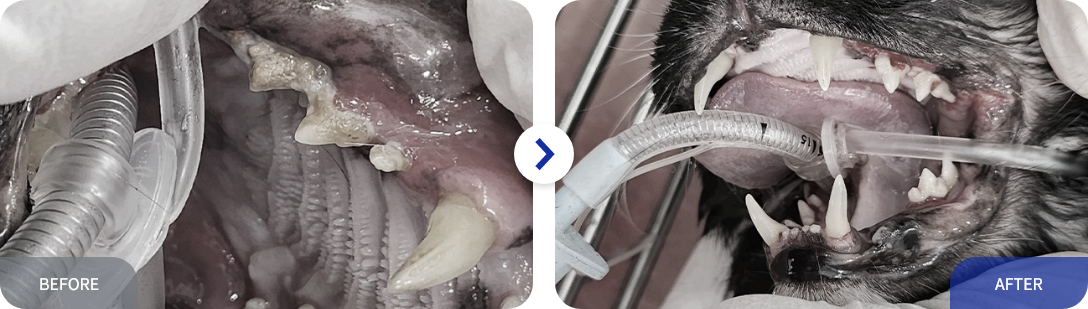

잔존 유치

생후 4개월령 이후부터 영구치가 맹출 되면서 유치가 빠지기 시작합니다.

7개월령까지 유치가 빠지지 않는다면, 영구치의 맹출을 방해할 수 있으며,

이후 치주 질환의 원인이 될 수 있습니다.